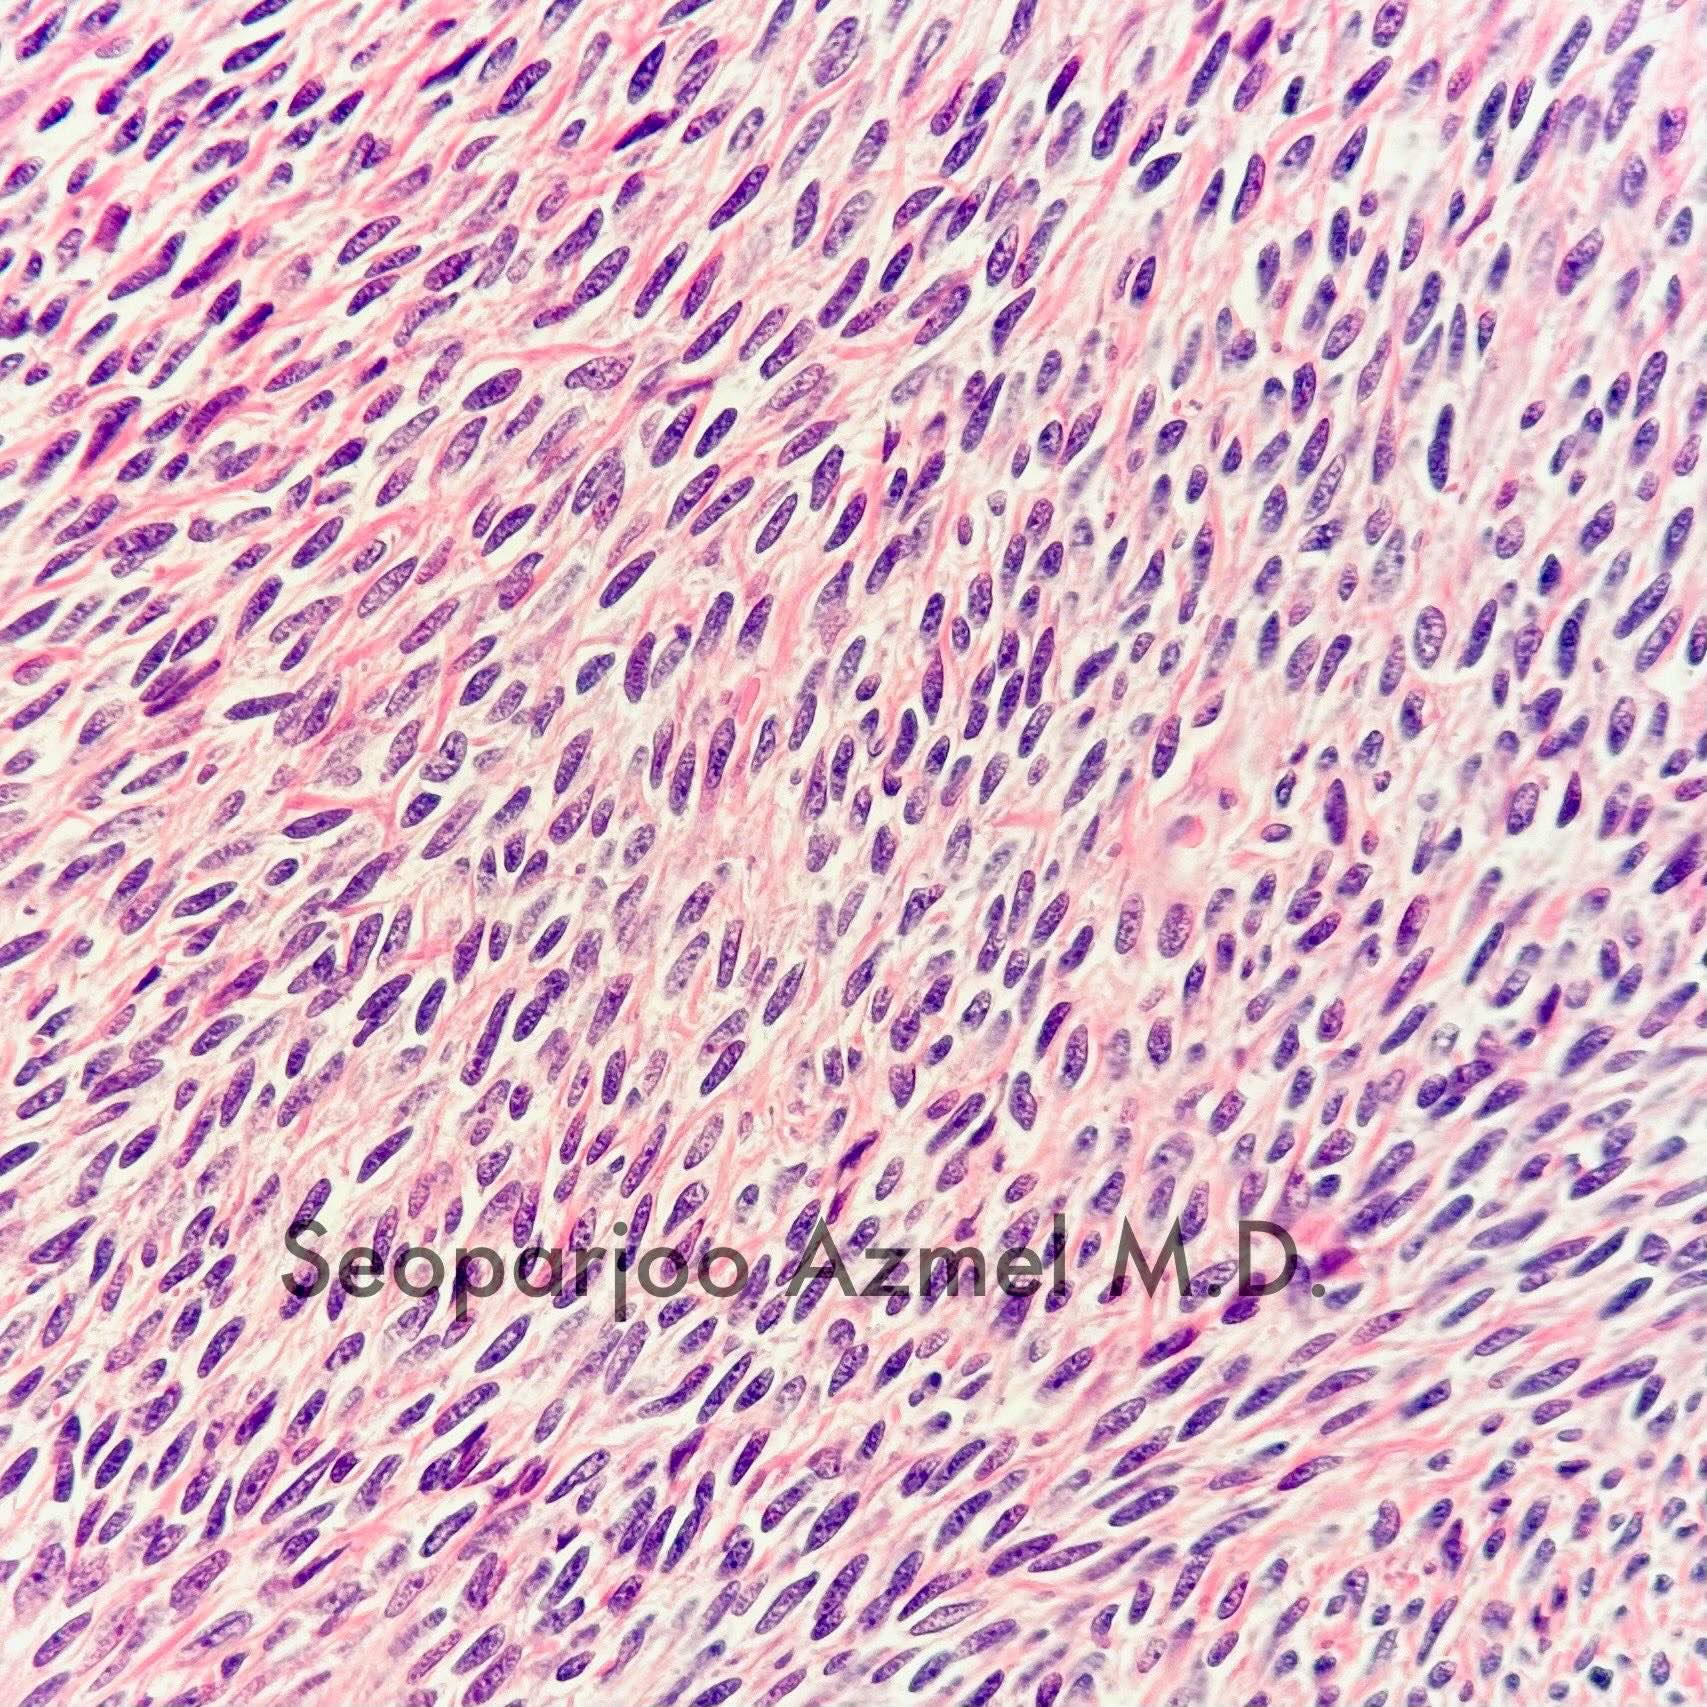

Microscopic (histologic) description

- Predominant population of cells showing ovoid to round nuclei and pale gray cytoplasm, which can be abundant

- Minor component of the tumor may have spindled nuclei, reflecting overlap between fibroma and thecoma

- Indistinct cell membranes impart a syncytial appearance

- Diffuse or nodular growth pattern

- Absent or minimal nuclear atypia

- Mitotic rate usually < 5/10 high power fields

- Hyaline plaques

- Cytoplasmic lipid vacuoles may be present but are not essential

- May show aggregates of cells with brightly eosinophilic cytoplasm (lutein cells)

- Calcification is more common in young patients (Int J Gynecol Pathol 1988;7:343)

- Uncommon features include keloid-like sclerosis, nuclear grooves, bizarre nuclear atypia (Am J Surg Pathol 2014;38:1023)

- Rarely contains a minor component of sex cord elements (Int J Gynecol Pathol 1983;2:227)

- Malignant thecoma: very rare, diagnosis requires diffuse moderate to severe nuclear atypia and high mitotic rate (> 4/10 high power fields) (Am J Surg Pathol 2011;35:e15)

Microscopic (histologic) images

Contributed by Victoria Collins, M.D., Tamara Kalir, M.D., Ph.D., AFIP and @SeoparjooAzmel on Twitter